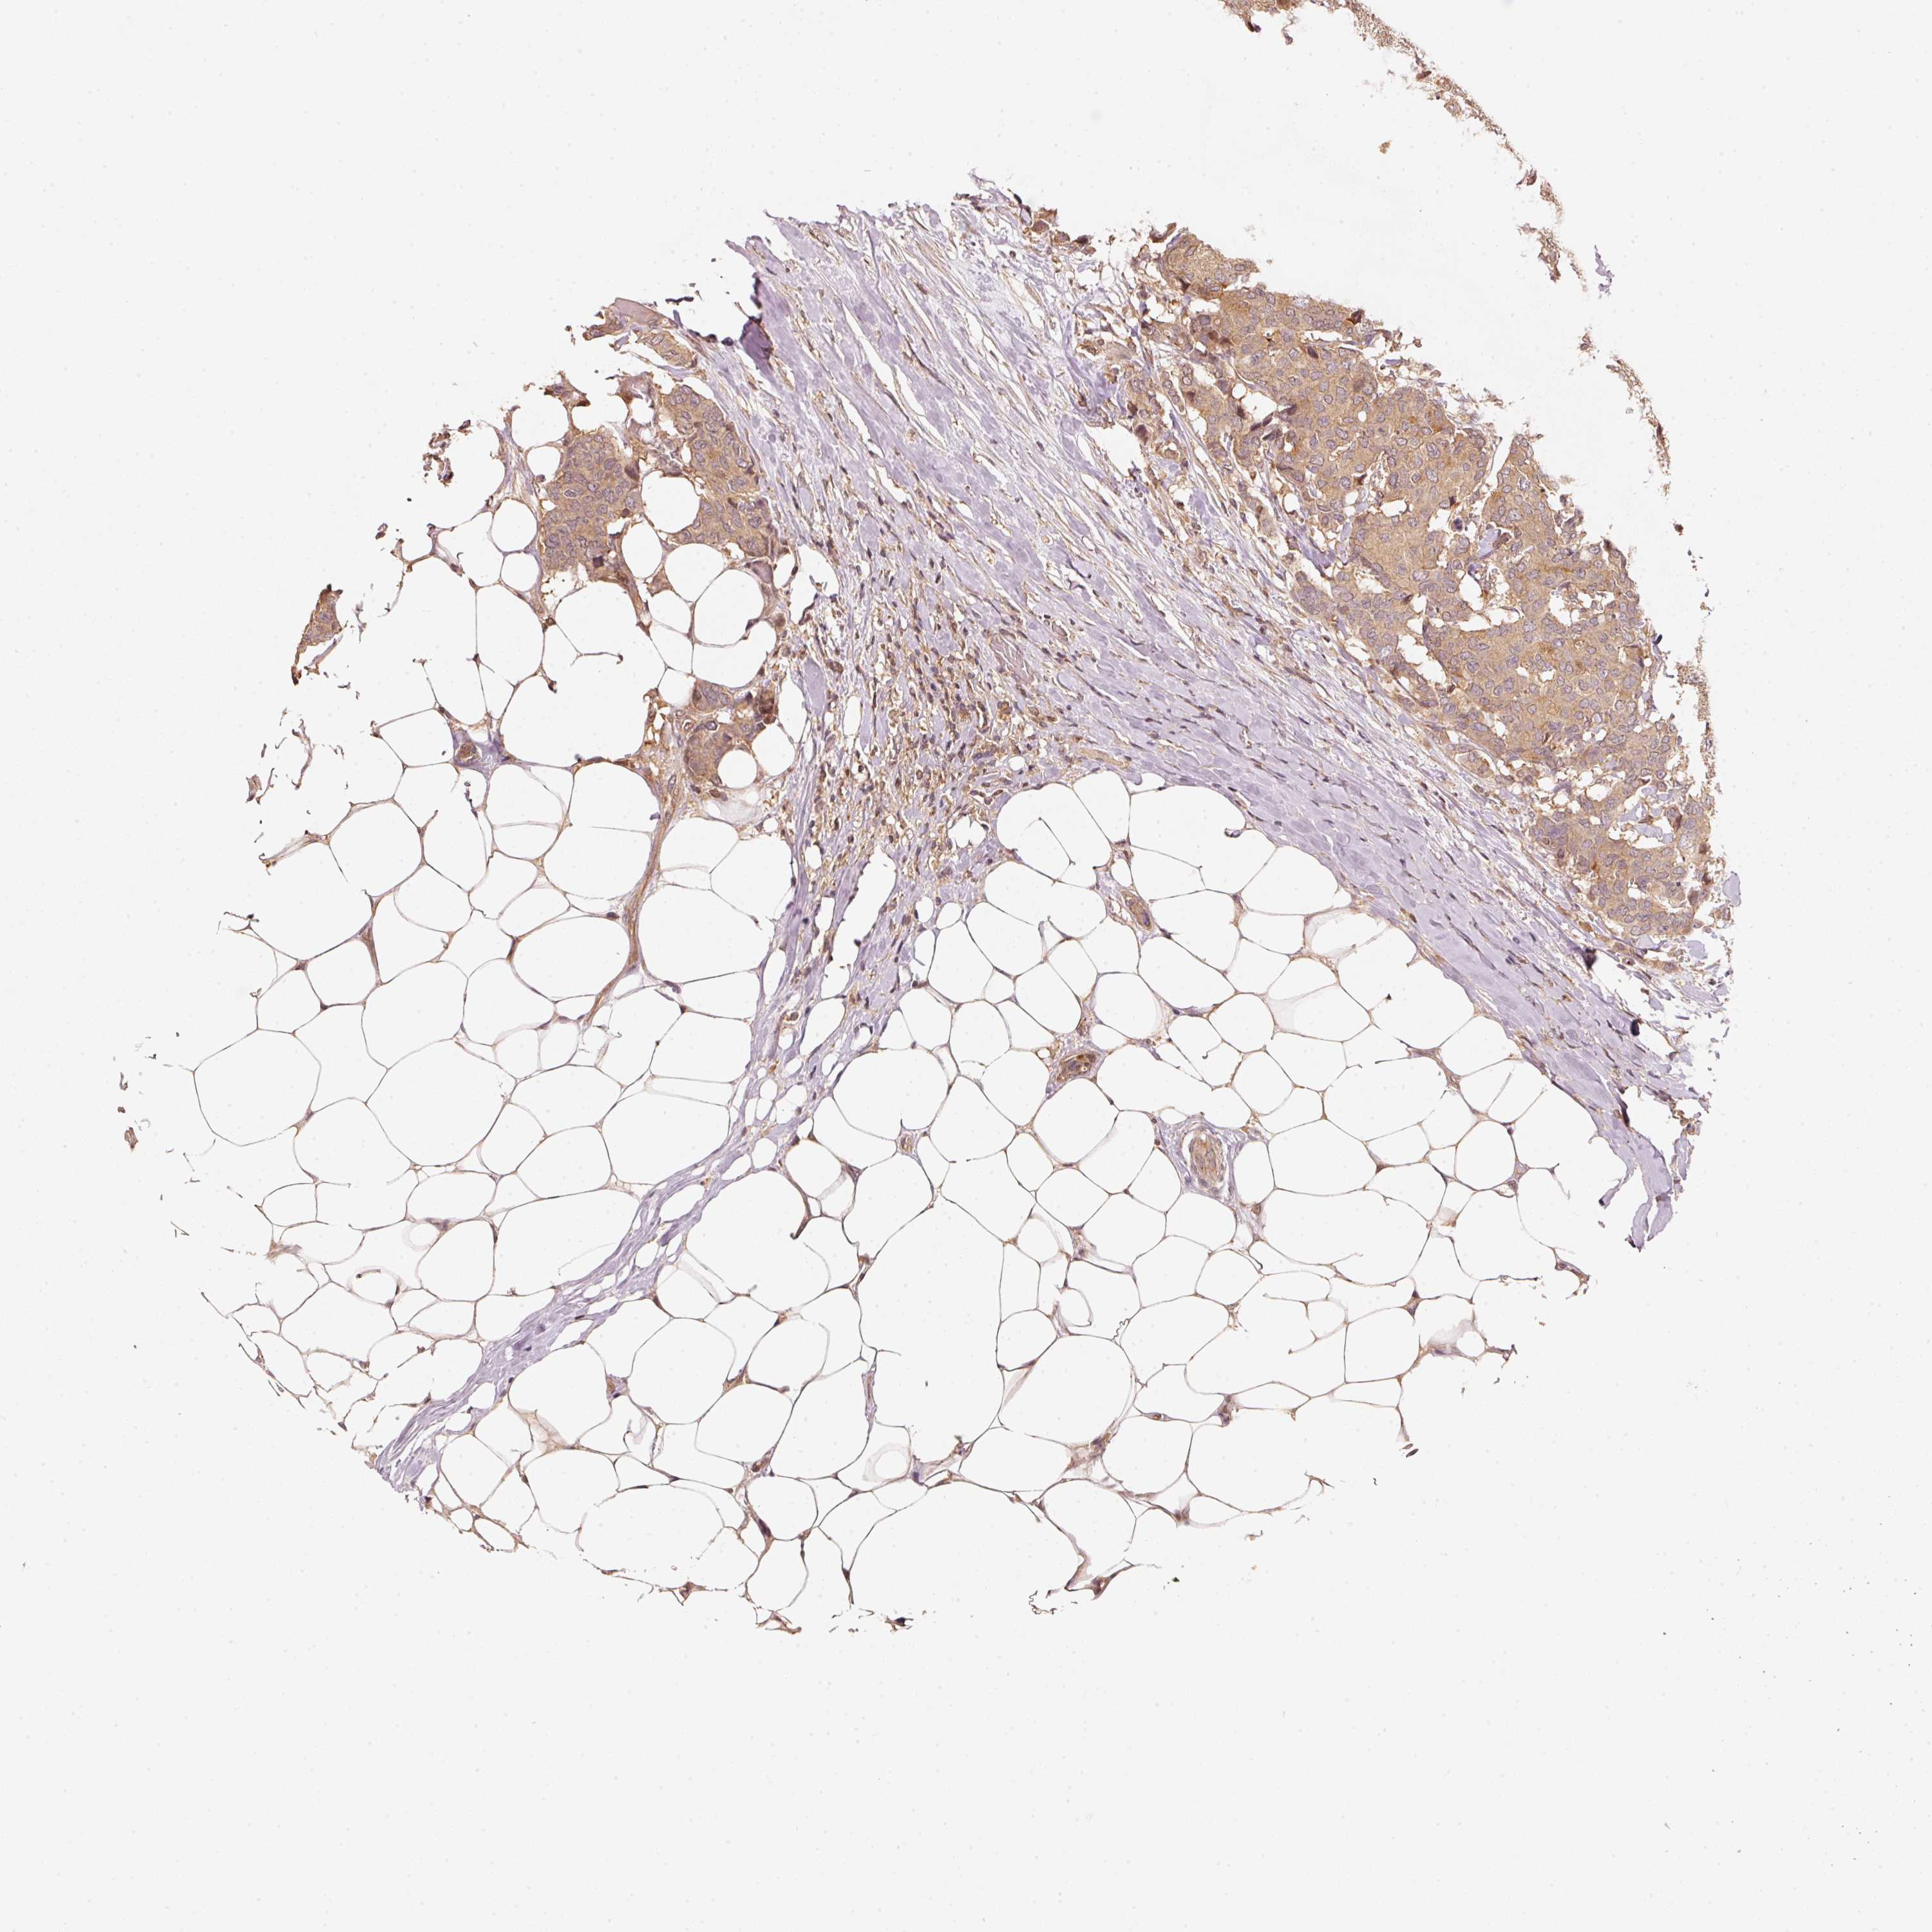

CANCER BREAST CANCER Show tissue menu

BRCA TCGA BRCA VALIDATION PROTEIN EXPRESSION